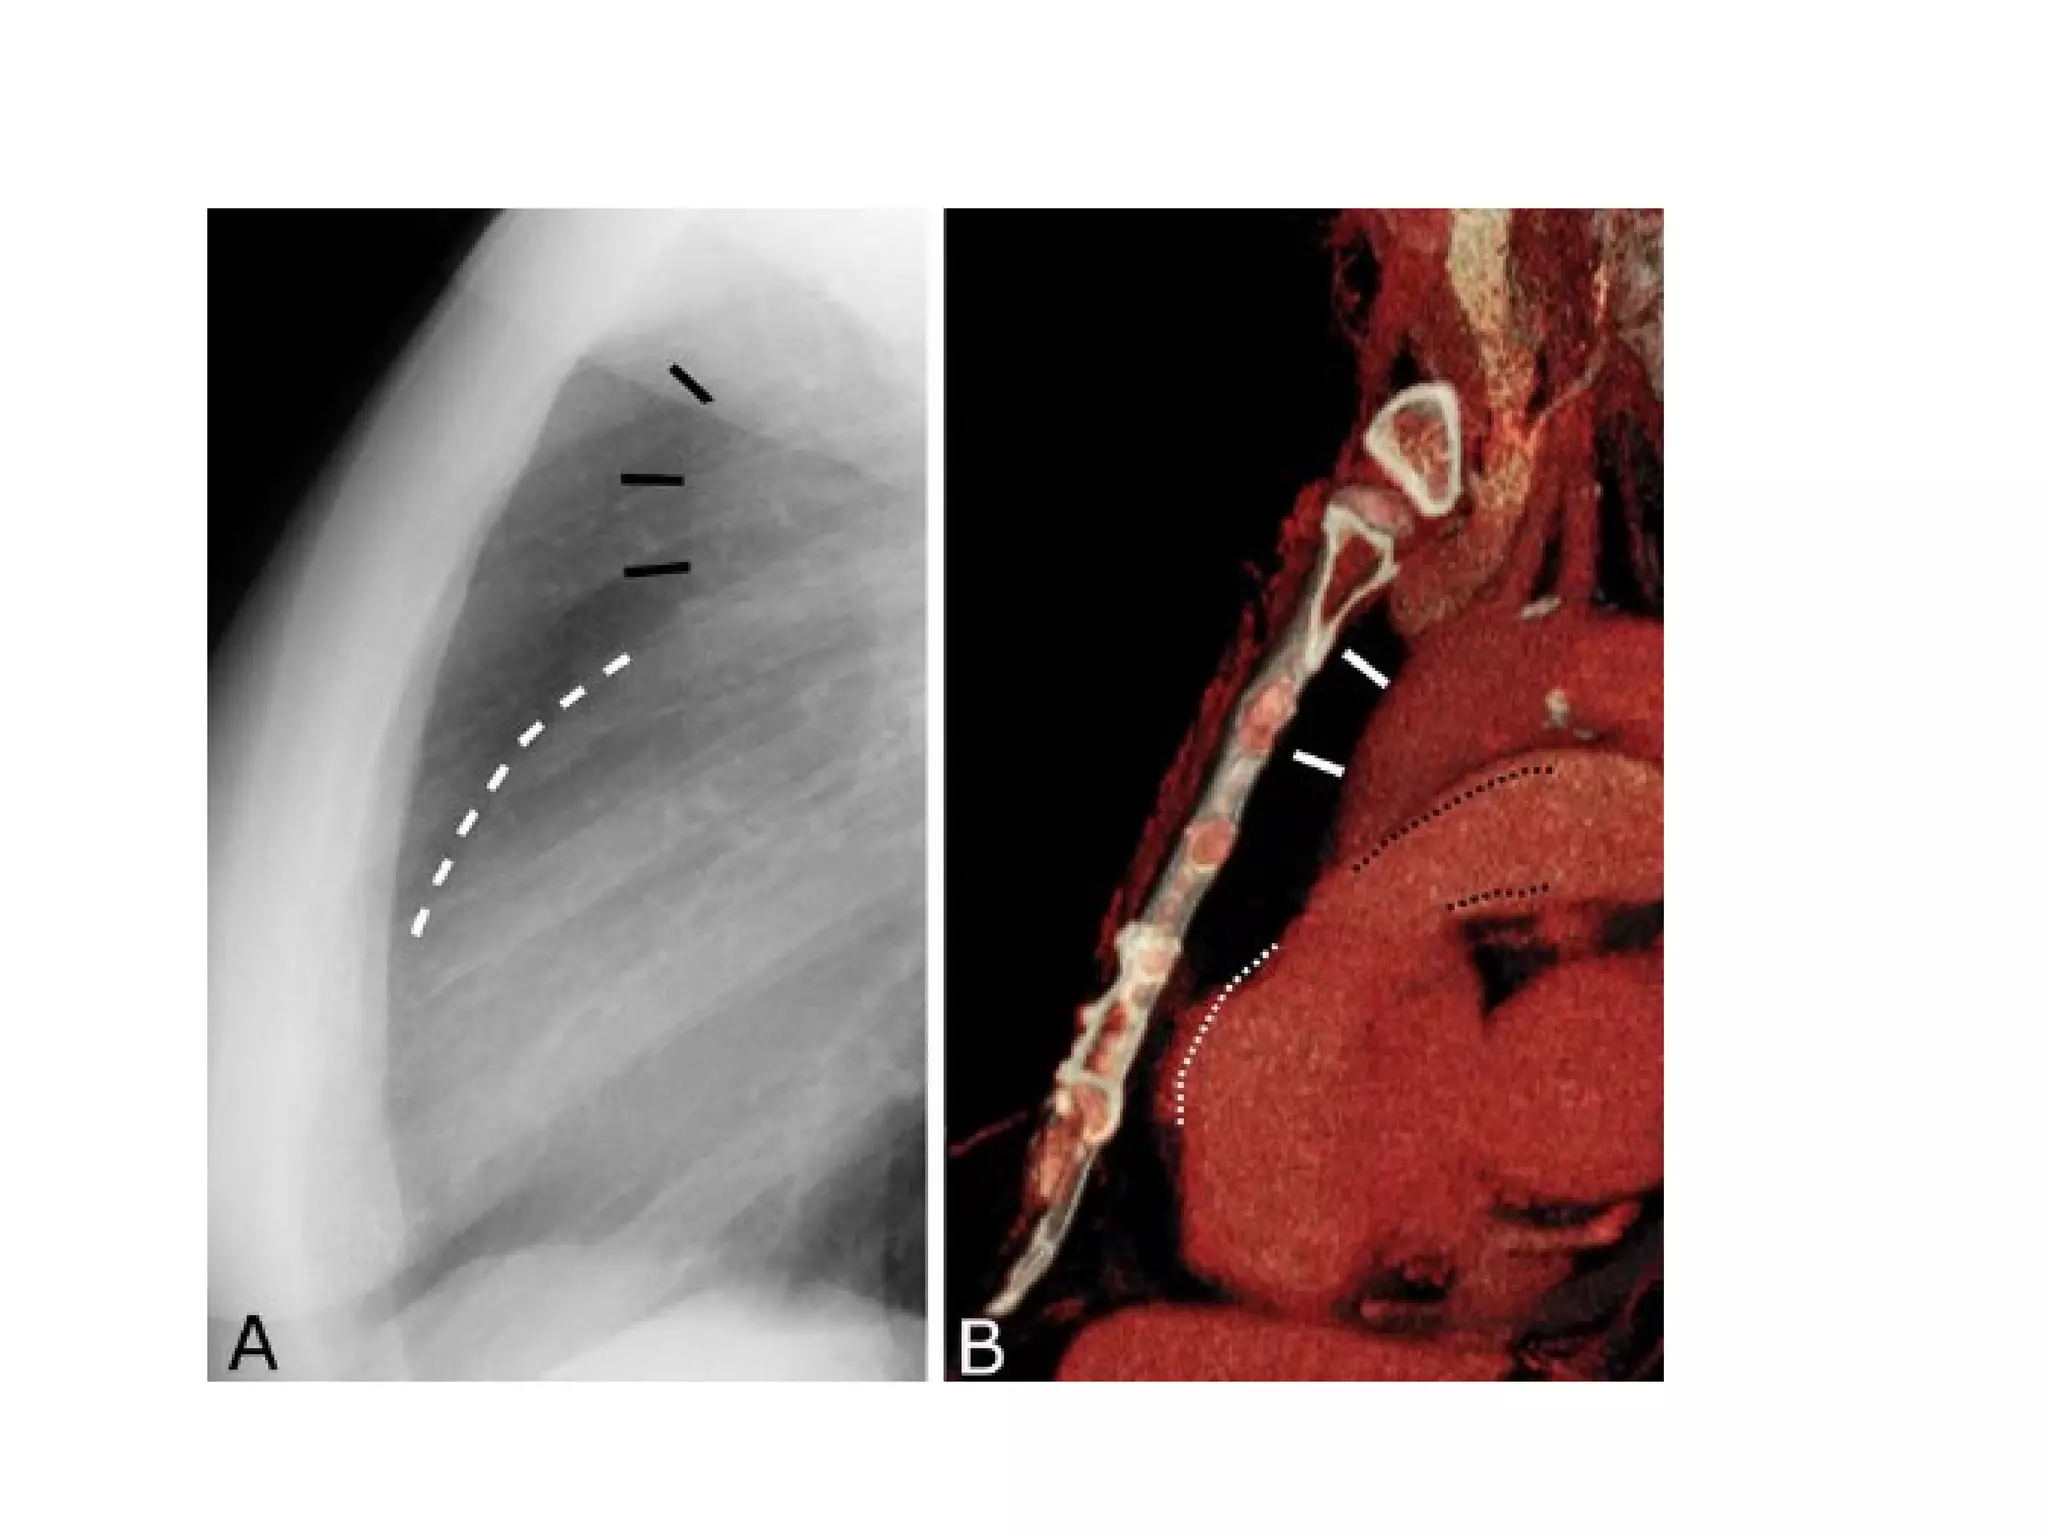

Viewing the lateral film

• Routinely the left side is adjacent to the

film

lateral

• Aortic arch

• Right pulmonary

artery

• Left pulmonary

• Trachea & bronchi

Image credit: Curry International Tuberculosis Center, University of California, San Francisco   23

• The clear spaces

Retrosternal space normally this space is less than 3 cm

deep

Retrocardiac space

• Vertebral translucency

The vertebral bodies become more

translucent caudally

• Diaphragm outline

Both diaphragms are visible

The posterior costophrenic angles are acute

and small amounts of pleural fluid may be

Viewing the lateralfilm • Routinely the left side is adjacent to the film

• Aortic arch • Right pulmonary artery • Left pulmonary artery • Trachea & bronchi Image credit: Curry International Tuberculosis Center, University of California, San Francisco 23

• The clearspaces Retrosternal space normally this space is less than 3 cm deep Retrocardiac space

• Vertebral translucency Thevertebral bodies become more translucent caudally

• Diaphragm outline Bothdiaphragms are visible The posterior costophrenic angles are acute and small amounts of pleural fluid may be detected.

• The trachea Thispasses down in a slightly posterior direction.